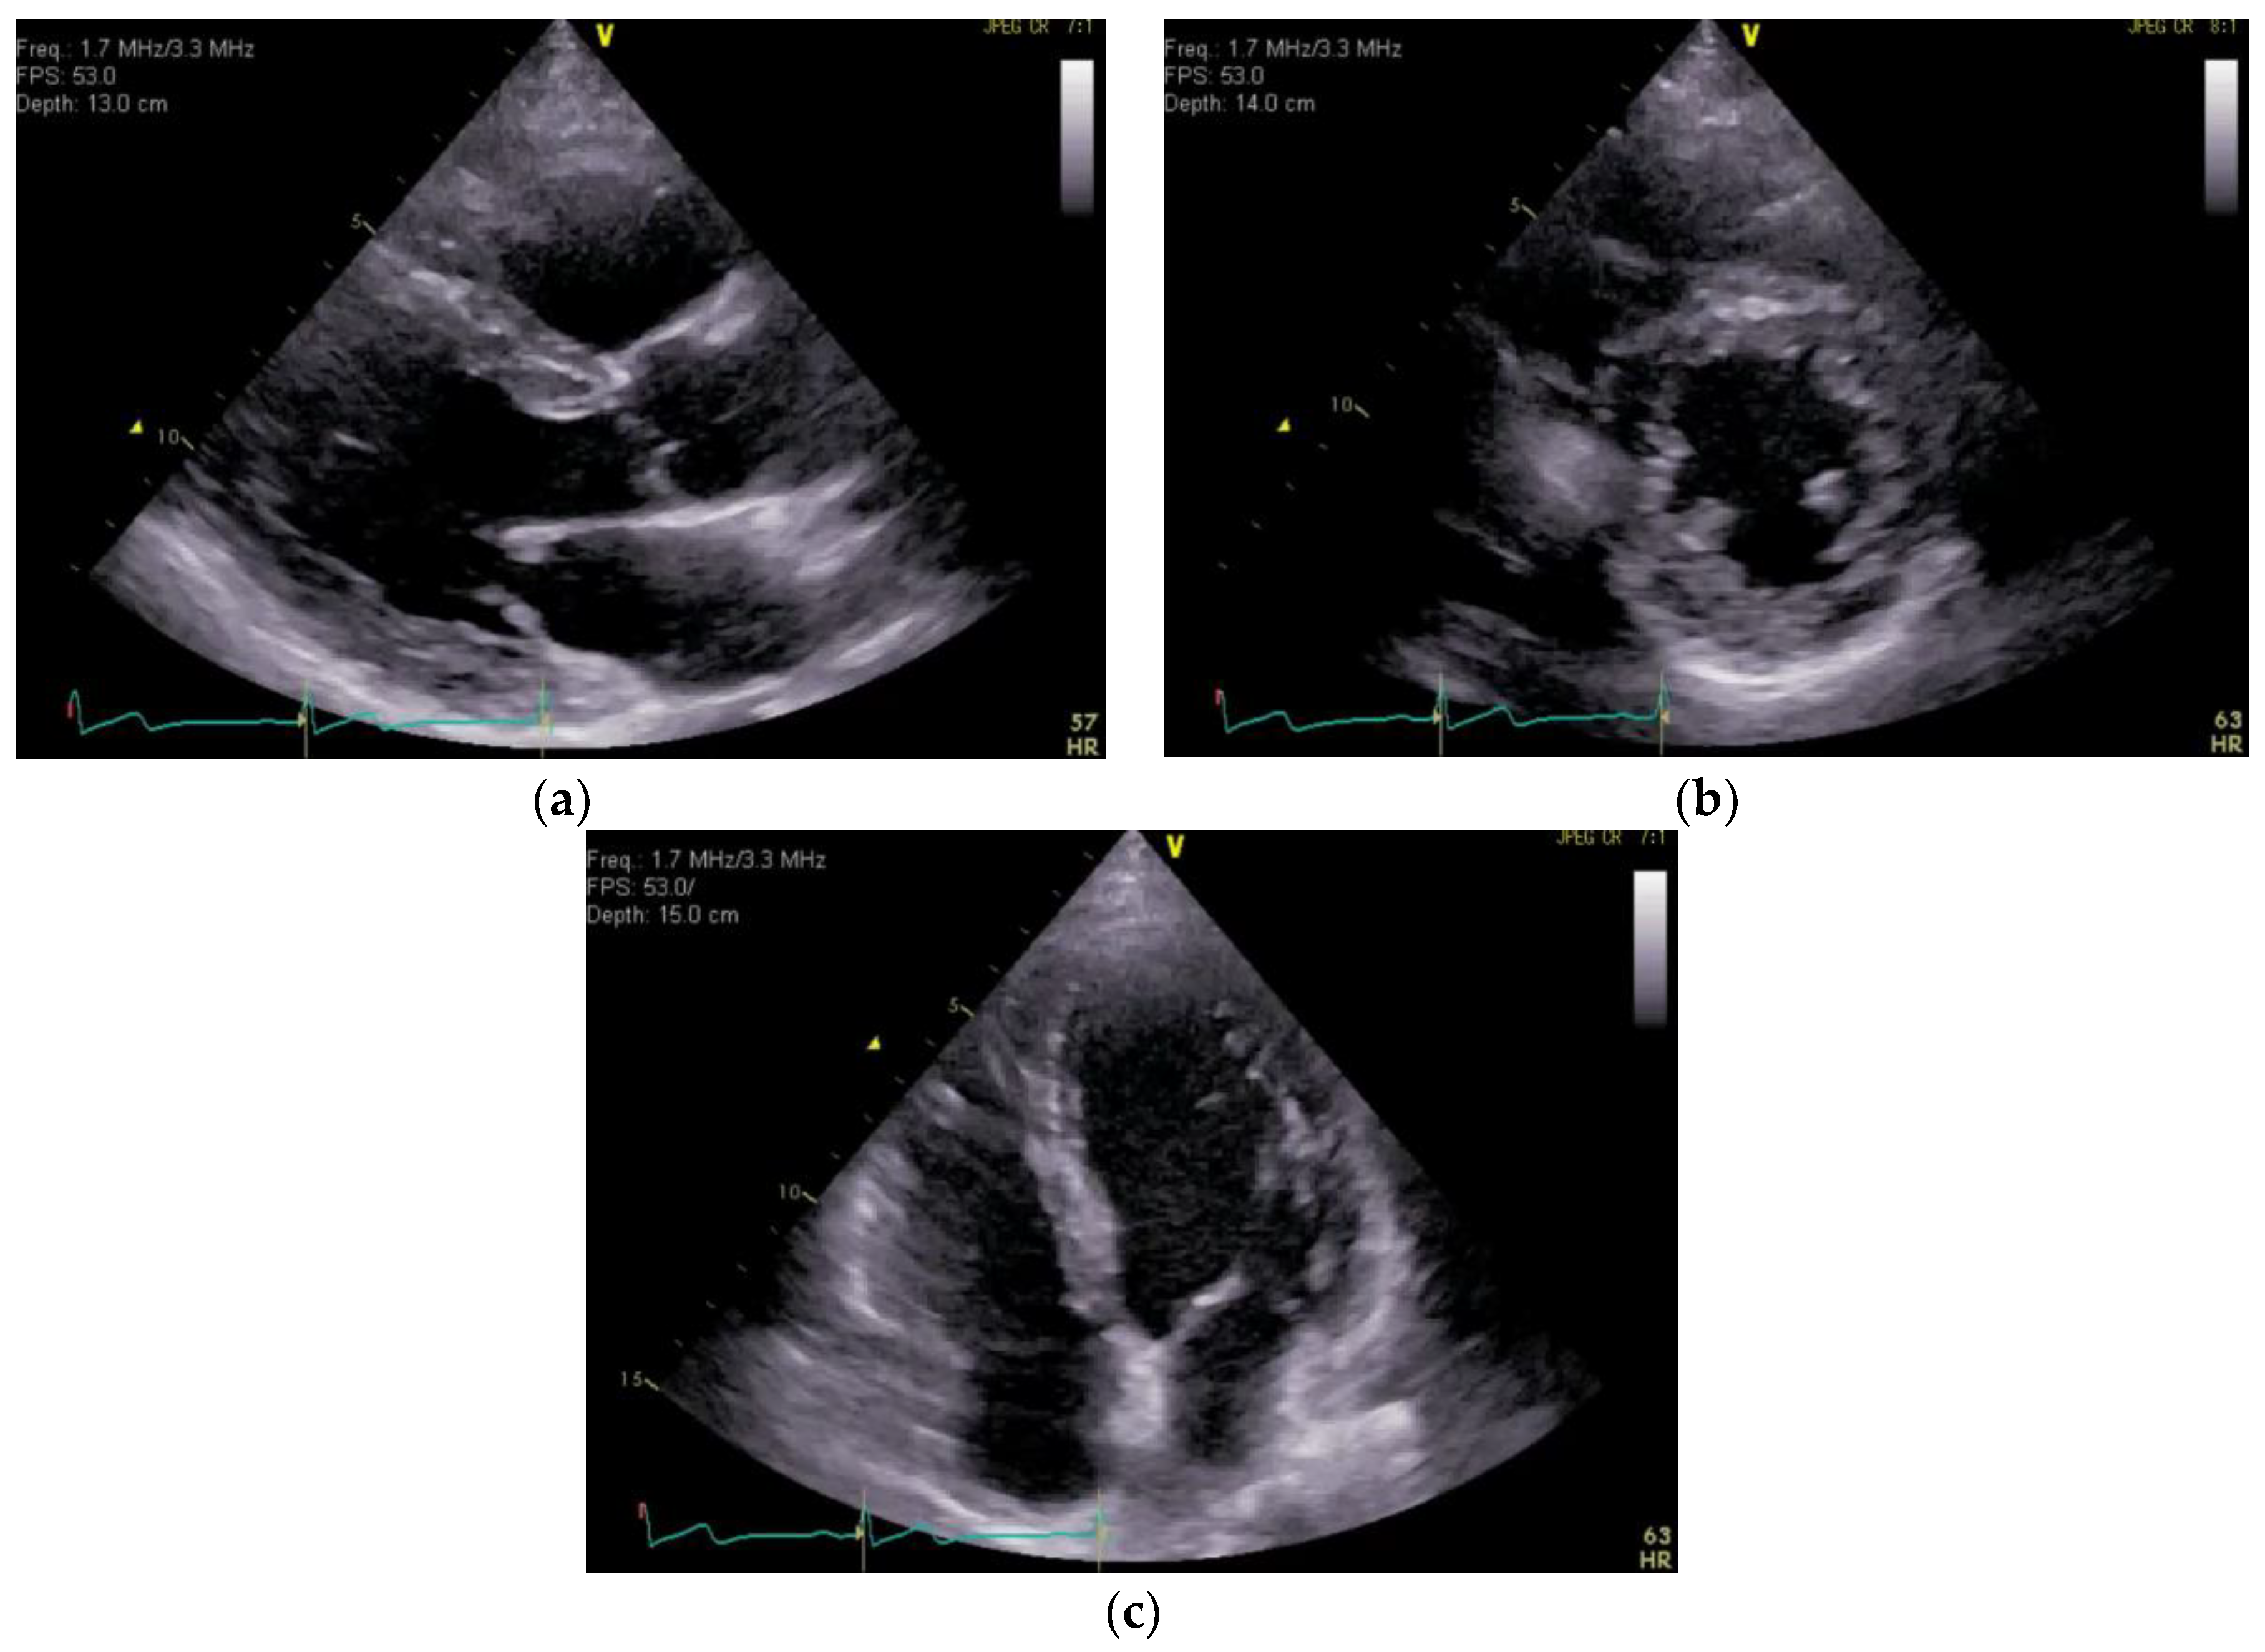

On the 12-lead ECG, heart rate of 98 beats/min, sinus rhythm, a positive axis, clear Q waves, and negative T waves during induction III were observed. Chest radiography (Figure 1) demonstrated slightly increased permeability in the bilateral middle lung fields. In transthoracic echocardiography (Figure 2), both left and right ventricles were of normal in size, as seen on the parasternal left border long-axis tomogram and parasternal left border short-axis tomogram, with no evidence of left ventricular compression. In the four-chamber view, the right ventricle seemed to be slightly enlarged. The tricuspid valve systolic pressure gradient was 22.5 mmHg. Chest contrast-enhanced CT revealed thrombi in the bilateral main pulmonary arteries (Figure 3). Abdominal contrast-enhanced CT revealed thrombi in the IVC duplication, left common iliac vein, left IVC, and left renal vein (Figure 4). The left IVC was slightly smaller in diameter than the normal IVC (right IVC). It branched from the left renal vein and descended alongside the left kidney to contact the left common iliac vein. A tributary branch to the right IVC was observed immediately before it joined the left common iliac vein. The left femoral vein similarly demonstrated a few low-absorption areas, suggestive of thrombi.

Figure 1. Chest radiograph. Patient’s chest radiography performed on admission and demonstrating slightly increased permeability in the middle lung fields bilaterally.